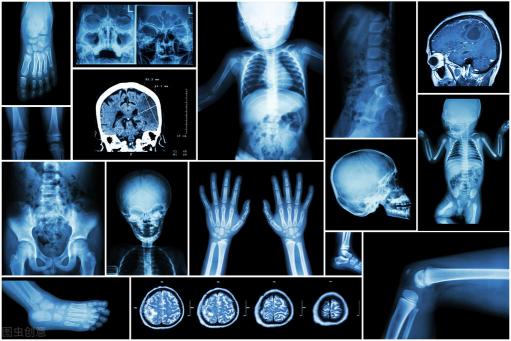

#监护仪#颅内压监护仪是用来连续测量人体颅内压(ICP)的医用设备,可与脑硬膜外、脑硬膜下、脑室内光纤探头相配,对脑硬膜内、外及婴儿囟门进行颅内压力监测,可以分为无创颅内压监护仪和有创两种颅内压监护仪。

新思界产业研究中心整理发布的《2020-2024年中国无创颅内压监护仪行业市场行情监测及未来发展前景研究报告》显示,脑室内有创ICP监测被认为是ICP监测的金标准,也是ICU中患者的标准管理方案。但是有创ICP监测有一定风险,并且有一定技术难度。由于侵入性、高成本以及有创ICP监测方法的其他附加风险,行业寻求替代的非侵入性技术监测ICP。由于缺乏熟练的专业人员,在某些情况下(例如紧急情况)使用侵入性技术是不可行的。无创ICP监测是一种替代方法,可以在颅骨外监测。无创ICP监测主要包括经颅多普勒超声、鼓室膜位移和视神经鞘直径等技术,一般作为有创监测的补充方案。 近年来,由于全球神经系统疾病(如颅内肿瘤、脑积水、脑部感染、动脉瘤和脑膜炎等)发病率上升以及交通事故导致的颅脑损伤事故增加,对于微创外科手术需求增长,新技术的推出以及创伤护理导致对于无创颅内压监测仪需求增长。此外全球老年人口的高速增长也推动了无创颅内压监测仪的需求,老年人口容易出现各种神经系统疾病以及脑外伤。因此,预计今后几年,全球老年人口的增加将成为影响市场的重要因素。

新思界行业研究员表示,根据技术不同,无创颅内压监测仪市场细分为经颅多普勒超声检查、鼓室膜位移(TMD)、和神经鞘管直径技术、MRI/CT和眼底镜检查。MRI/CT技术目前占据较大的市场份额,这些设备易于使用,并且在病理组织和正常组织之间具有高对比度,可提供更快、更安全的结果,并提供出色的图像。此外,由于MRI/CT扫描对ICPs升高的颅脑损伤患者进行评估的敏感性更高,因此是广泛首选的成像设备。因此,在神经疾病的诊断和分期中越来越多的应用及其相对于其他成像方式的优势推动了这一领域的发展。预计今后几年,视神经鞘管直径段技术将会成为发展最快的技术方式,这是由于视神经鞘管直径段技术是紧急医疗情况中最合适且广为应用的治疗方式。